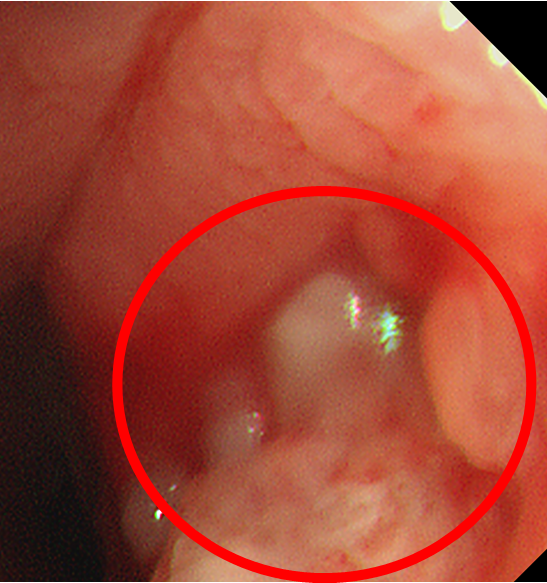

图2.气管镜下见左主支气管瘘口

结合胸部CT、气管镜检查所见,根据左主支气管瘘口的范围及程度,团队选取了适合的覆膜气道支架。